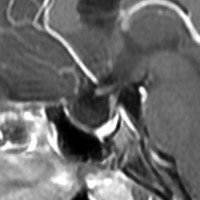

ラトケ嚢胞のMRIです。両耳側半盲という視野の障害(目がみづらい)で発症した女性のものです。左はT2強調画像と言います。右はガドリニウム造影剤を使ったものです。嚢胞のうすい壁だけが見えますが,中身は液体です。鼻孔から入って嚢胞をぷつんとつぶすだけの手術をします。薄い黄色の水のような液体が出ました。

手術後のMRIです。嚢胞はぺしゃんこになって視力は良くなりました。正常の下垂体は残っていてホルモンの障害もありません。